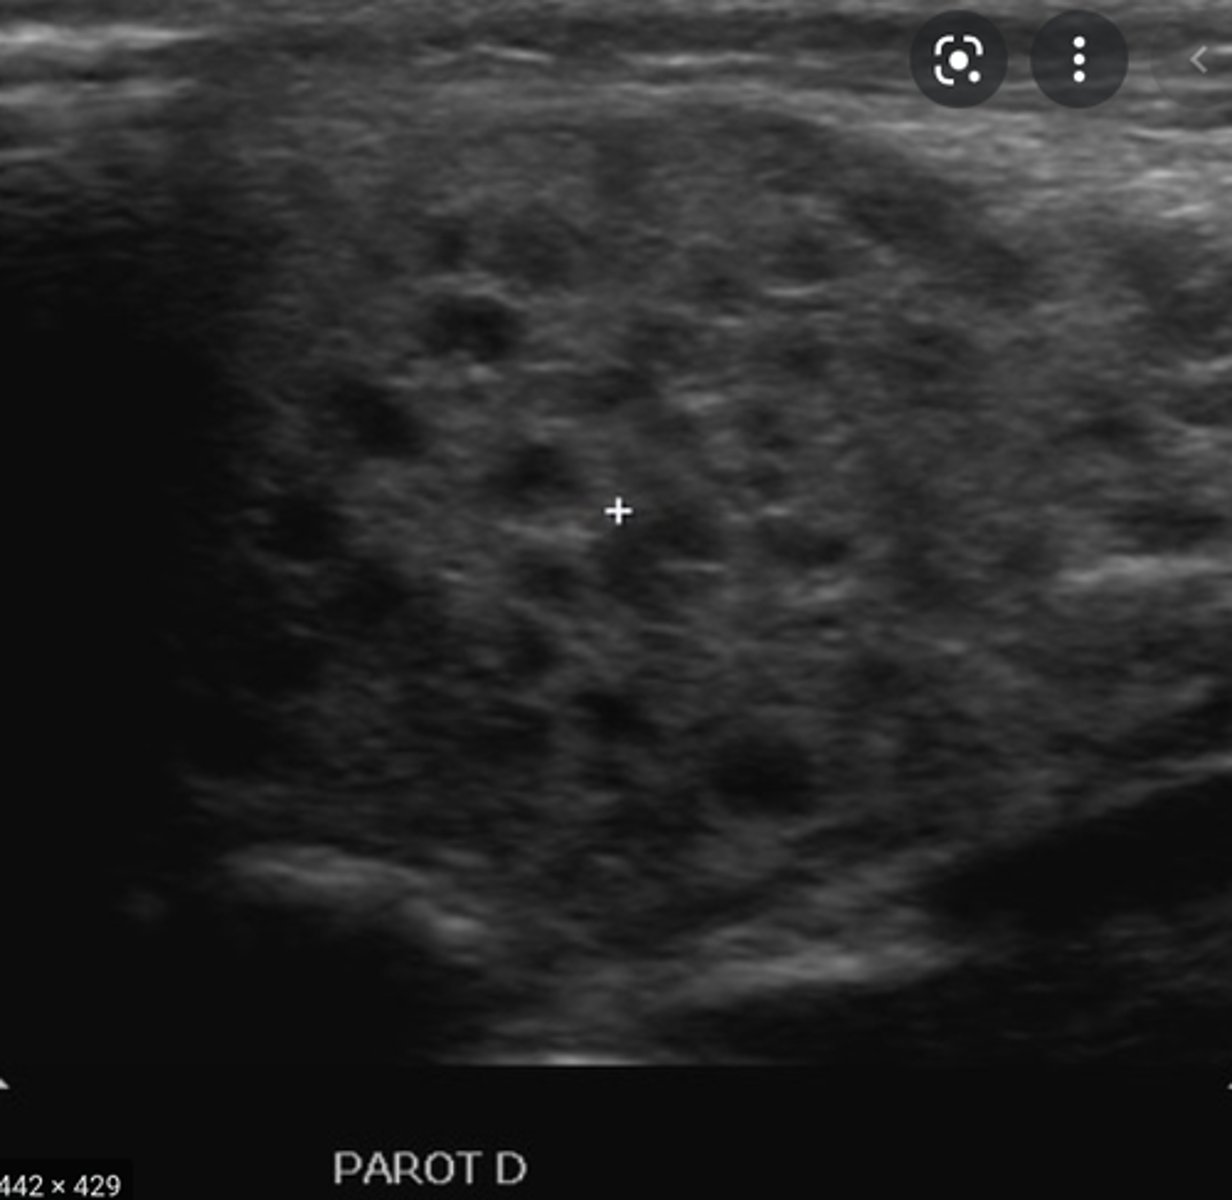

Location - Salivary Glands:

Parotid gland

-_____ to the ear near the ramus of the mandible

-_____ vein separates the superior and deep lobes of the gland

-Anterior to the ear near the ramus of the mandible

-Retromandibular vein separates the superior and deep lobes of the gland